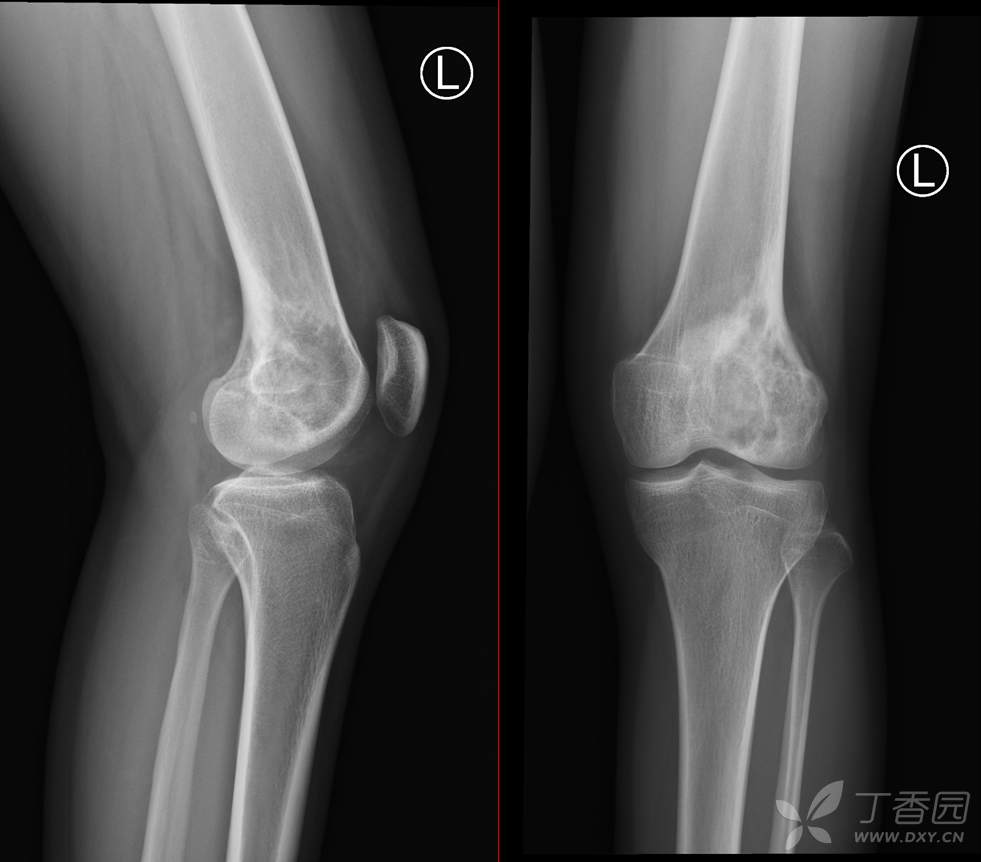

【影诊笔记497】左膝关节疼痛不适1周余就诊,有点难度~『骨巨细胞瘤』

主 诉:左膝关节疼痛不适1周余。

现病史:患者1周余前无明显原因及诱因出现左膝关节疼痛不适,活动时疼痛加重,休息后好转,无明显关节不稳及交锁,无发热、盗汗、乏力,无胸闷、憋气,无头痛、头晕,无四肢小关节晨僵。曾于外院就诊行左膝DR检查示:左股骨远端肿物。现患者为进一步治疗于我院就诊,门诊经检查后以“左股骨远端肿物”收入我科。患者自起病以来,神志清,精神可,饮食睡眠可,大小便正常,体重无明显减轻。